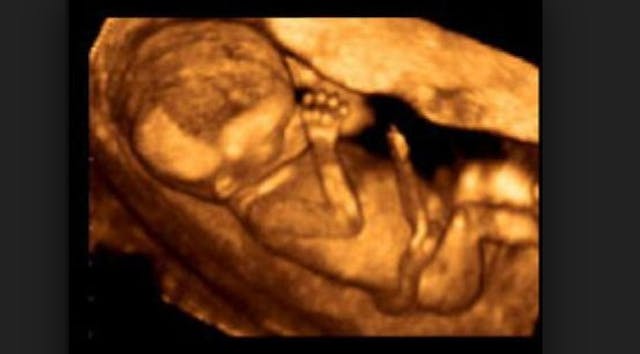

D&E, or dilation and evacuation abortion, is the most common second trimester abortion procedure. Over 125,000 are done every year in the United States. (1) Below is a procedure video featuring former abortionist Dr. Levatino, along with quotes from abortionists about this type of abortion:

This doctor has performed over 1,200 abortions. Now, he’s revealing what actually happens during a second trimester abortion procedure. This video may just change the abortion debate.